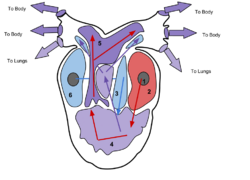

File:Flow through the Heart.webm File:Schematic 3D illustration of blood flow through the heart.ogg The heart functions as a pump in the circulatory system to provide a continuous flow of blood throughout the body. This circulation consists of the systemic circulation to and from the body and the pulmonary circulation to and from the lungs. Blood in the pulmonary circulation exchanges carbon dioxide for oxygen in the lungs through the process of respiration. The systemic circulation then transports oxygen to the body and returns carbon dioxide and relatively deoxygenated blood to the heart for transfer to the lungs.[7]

The right heart collects deoxygenated blood from two large veins, the superior and inferior venae cavae. Blood collects in the right and left atrium continuously.[7] The superior vena cava drains blood from above the diaphragm and empties into the upper back part of the right atrium. The inferior vena cava drains the blood from below the diaphragm and empties into the back part of the atrium below the opening for the superior vena cava. Immediately above and to the middle of the opening of the inferior vena cava is the opening of the thin-walled coronary sinus.[7] Additionally, the coronary sinus returns deoxygenated blood from the myocardium to the right atrium. The blood collects in the right atrium. When the right atrium contracts, the blood is pumped through the tricuspid valve into the right ventricle. As the right ventricle contracts, the tricuspid valve closes and the blood is pumped into the pulmonary trunk through the pulmonary valve. The pulmonary trunk divides into pulmonary arteries and progressively smaller arteries throughout the lungs, until it reaches capillaries. As these pass by alveoli carbon dioxide is exchanged for oxygen. This happens through the passive process of diffusion.

In the left heart, oxygenated blood is returned to the left atrium via the pulmonary veins. It is then pumped into the left ventricle through the mitral valve and into the aorta through the aortic valve for systemic circulation. The aorta is a large artery that branches into many smaller arteries, arterioles, and ultimately capillaries. In the capillaries, oxygen and nutrients from blood are supplied to body cells for metabolism, and exchanged for carbon dioxide and waste products.[7] Capillary blood, now deoxygenated, travels into venules and veins that ultimately collect in the superior and inferior vena cavae, and into the right heart.